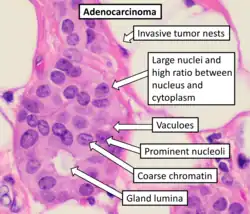

Most cancers are initially recognized either because of the appearance of signs or symptoms or through screening.[125] Neither of these leads to a definitive diagnosis, which requires the examination of a tissue sample by a pathologist.[126] People with suspected cancer are investigated with medical tests. These commonly include blood tests, X-rays, (contrast) CT scans and endoscopy.

The tissue diagnosis from the biopsy indicates the type of cell that is proliferating, its histological grade, genetic abnormalities and other features. Together, this information is useful to evaluate the prognosis and to choose the best treatment.

Cytogenetics and immunohistochemistry are other types of tissue tests. These tests provide information about molecular changes (such as mutations, fusion genes and numerical chromosome changes) and may thus also indicate the prognosis and best treatment.

Classification

Cancers are classified by the type of cell that the tumor cells resemble and is therefore presumed to be the origin of the tumor. These types include:

- Carcinoma: Cancers derived from epithelial cells. This group includes many of the most common cancers and include nearly all those in the breast, prostate, lung, pancreas and colon. Most of these are of the adenocarcinoma type, which means that the cancer has gland-like differentiation.

Cancers are usually named using -carcinoma, -sarcoma or -blastoma as a suffix, with the Latin or Greek word for the organ or tissue of origin as the root. For example, cancers of the liver parenchyma arising from malignant epithelial cells is called hepatocarcinoma, while a malignancy arising from primitive liver precursor cells is called a hepatoblastoma and a cancer arising from fat cells is called a liposarcoma. For some common cancers, the English organ name is used. For example, the most common type of breast cancer is called ductal carcinoma of the breast. Here, the adjective ductal refers to the appearance of cancer under the microscope, which suggests that it has originated in the milk ducts.

Some types of cancer are named for the size and shape of the cells under a microscope, such as giant cell carcinoma, spindle cell carcinoma and small-cell carcinoma.

Squamous cell carcinoma with typical histopathology features.

Squamous cell carcinoma with typical histopathology features. -